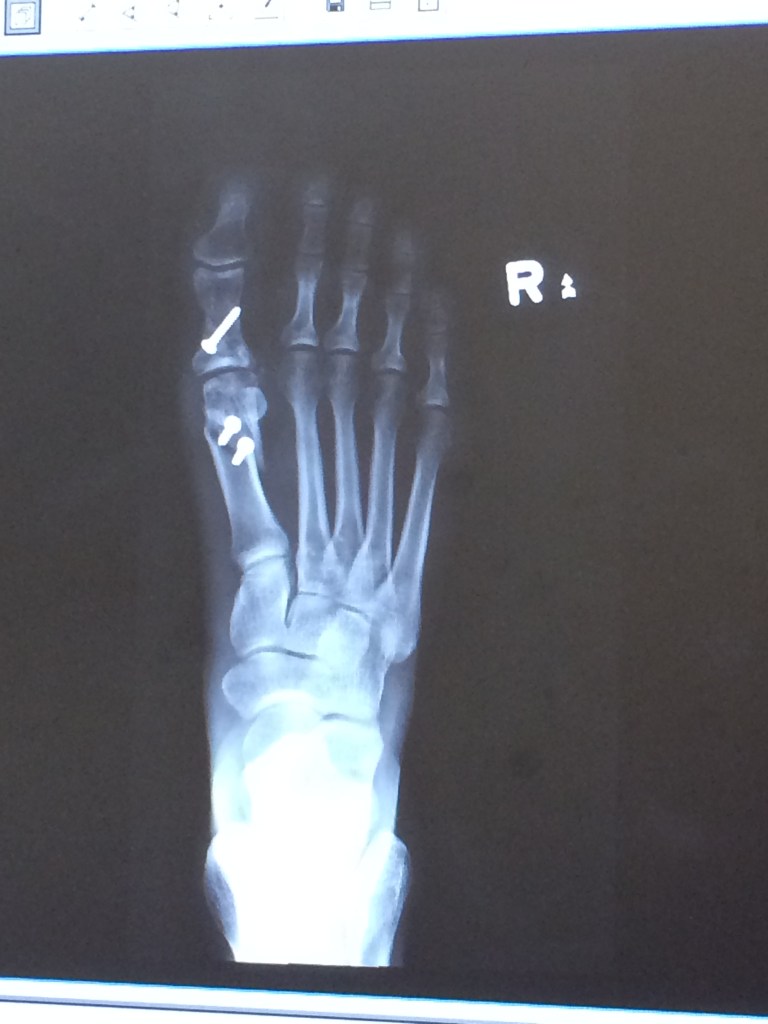

So…How is my foot doing now???